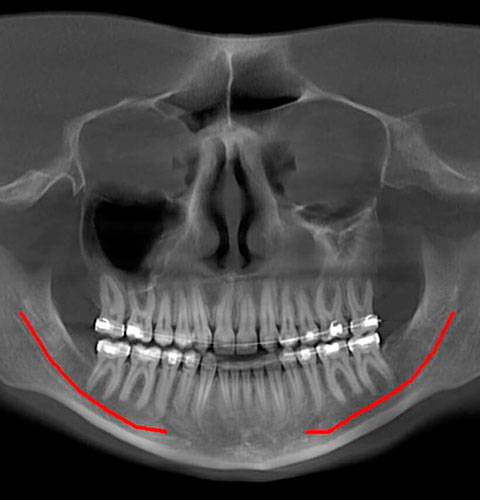

Veja exemplos de diagnósticos de imagem

- O gerador com ânodo giratório e ponto focal de 0,3 mm permite obter imagens de altíssima definição para ver detalhes e microestruturas que não podem ser investigados com dispositivos tecnológicos padrão;

- Algoritmos de reconstrução e processamento de imagem, resultado dos vinte anos de experiência da NewTom, permitem obter rapidamente imagens 2D e 3D excepcionais.